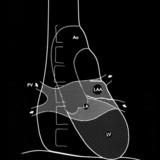

Gallery Cardiac

Cardiac

Cong Ht Disease

Album: Cong Ht Disease

Mitral Valve Disease

Album: Mitral Valve Disease